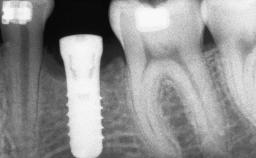

Ridge Preservation and Implant Placement for a Fixed Dental Prosthesis After a Car Accident

It is well known to clinicians that any removal of teeth will, over time, cause the dimensions of the alveolar ridge to be reduced by resorption of the bundle bone and by changes related to external modeling. This development is particularly evident in the crestal region with its thin buccal bone that consists of bundle bone almost entirely. The facial bone will rapidly resorb as blood supply from the periodontal ligament gets disrupted (Araújo and Lindhe 2005). There is no reason why traumatic tooth loss should not have the same consequences. It takes more than achieving implant osseointegration for a treatment outcome to be considered successful. No deficiency of bone or soft tissue is acceptable when an ideal esthetic outcome is the goal. Several articles (Sanz and coworkers 2011; Vignoletti and coworkers 2011) have reported on techniques of improving the alveolar ridge for implant treatment, notably focusing on protecting tissues from resorption.

Bone Augmentation Horizontal|Simultaneous|Sinus Floor Elevation|Staged

Augmentation Materials Xenogenous|Membrane